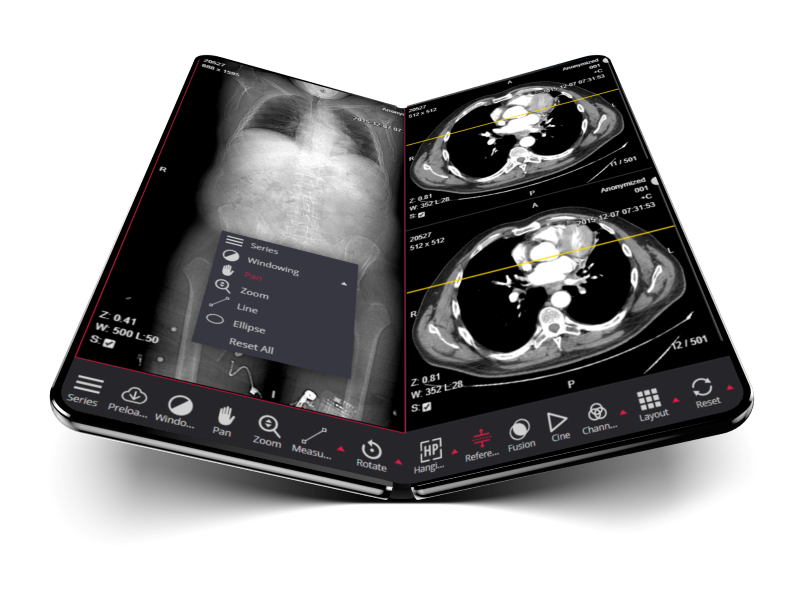

DICOM 3.0 compliant picture archiving and communication system. The PACS server provides connectivity to all DICOM modalities (CR, DX, CT, MR, US, XA, etc.). Review of DICOM images and diagnostics can be done using the MedDream WEB DICOM Viewer.Go to SitePad Editor to add your own text and edit me. It’s easy. Just Go to SitePad Editor to add your own text and edit me content and make changes to the font.